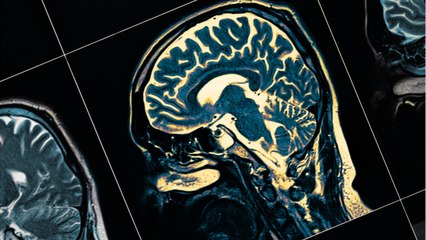

Too Much Napping Could Be br Linked to Alzheimer's Disease A new study has found a connection betweenbr increased daytime tiredness and early signsbr of the memory-loss health issue. The analysis can be found in 'Alzheimer's & Dementia: Journal of the Alzheimer's Association.' For their study, researchersbr observed 13 brains from peoplebr who died with Alzheimer's. Against seven other brains without the disease, br they found that organ parts which keep br us awake during the day were weaker. Scientists say they are still unclear on the lengthbr of time between increased daytime sleepiness br and the onset of Alzheimer's disease. They concluded that morebr studies on the link needbr to be conducted.